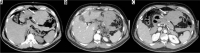

Purpose: The aim of study is to identify the frequency of acute complications and imaging findings at gastro-intestinal transit (GI) and computerised tomography (CT) in a group of obese patients who developed clinical suspicion of acute complications (painful and meteoric abdomen, nausea, vomiting, fever, intestinal blockage) in post bariatric surgery.

Material and methods: We retrospectively review 954 obese patients who underwent bariatric surgery between 2013 and 2019. The study included 72 patients who developed clinical suspicion of acute complications (painful and meteoric abdomen, nausea, vomiting, fever, intestinal blockage) within 6 days of bariatric surgery of sleeve gastrectomy, gastric banding, gastric bypass with Roux loop confirmed by CT, and who underwent a gastrointestinal transit before the CT examination.

Results: GI exam allowed visualisation of 58% of complications. Analysing the data for each surgical technique, 46 post-operative complications were found involve gastric banding. The most frequent was bandage migration (26 cases, 56 %), identified in all cases at GI transit and then confirmed on CT.